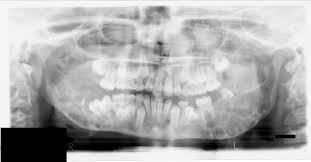

Cherubism In 8 Years Old Child Treatment Experience Medcrave Online

Cherubism In 8 Years Old Child Treatment Experience Medcrave Online from medcraveonline.com

Through the influence of the septuagint, cherubim was used in the earlier english versions, also as a singular, hence, the plural was made to sound cherubims. Cherubism is a rare disorder characterized by progressive, painless, bilateral swelling of the jaw during childhood. Cherubism is a rare disorder characterized by progressive, painless, bilateral swelling of the jaw during childhood. Cherubism is a benign, hereditary giant cell lesion of the jaws, that appears in children as a bilateral painless swelling, between the ages of 2 and 5 years and progresses until puberty, when it spontaneously regresses. Fibrous dysplasia (fd) is a congenital disorder with a defect in osteoblastic differentiation and maturation, resulting in the replacement of normal cancellous bone by fibrous tissue and immature woven bone. Cherubism is a very rare bone disorder where bone gets resorbed only in the jaw bones (mandible and maxilla). Cherubism, a clinicopathological entity of genetic origin, predominantly affects the mandible, with maxillary involvement to a lesser degree. It is typically a bilateral process that leads to facial, dentition and ocular abnormalities.

The term cherubism was invented in 1933 by jones, who linked the full cheeks and the orbital displacement with the round faces and heavenly directed gaze of renaissance cherubs. Cherubism is a hereditary disease which is histologically similar to central giant cell granuloma occurs due to the following reasons: Affected children appear normal at birth. Cherubism is a rare genetic condition that affects the bones of your lower jaw and sometimes upper jaw. Cherubism is a disorder characterized by abnormal bone tissue in the jaw. Cherubism is a rare disorder characterized by progressive, painless, bilateral swelling of the jaw during childhood. Interestingly, penetrance is dependent on gender: Typically, cherubism is an isolated benign condition; The enlargement is usually symmetric in nature. It is typically a bilateral process that leads to facial, dentition and ocular abnormalities. Cherubism is a rare autosomal dominant disease of the jaw and maxilla. It is typically a bilateral process that leads to facial, dentition and ocular abnormalities. Cherubism is a benign, hereditary giant cell lesion of the jaws, that appears in children as a bilateral painless swelling, between the ages of 2 and 5 years and progresses until puberty, when it spontaneously regresses.